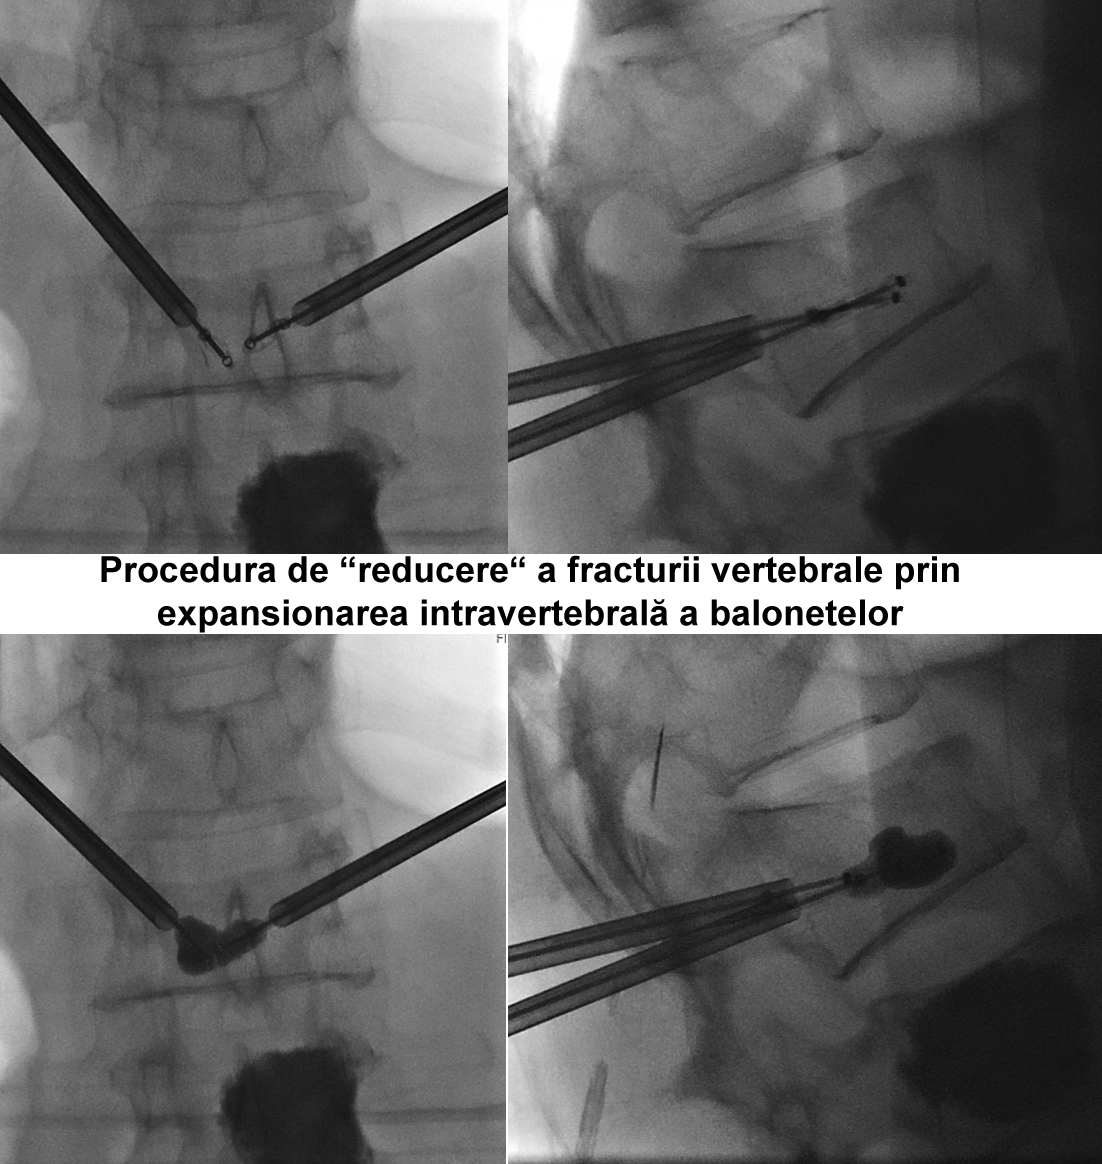

Kyfoplastia reprezintă o procedură minim invazivă în timpul căreia chirurgul introduce în corpul vertebral un tub cu un balon expandabil. Sub control fluoroscopic are loc expansionarea balonului în corpul vertebral, cu restabilirea înălţimii corpului vertebral şi corijarea diformităţii kifotice. Ulterior, în cavitatea formată de balon, se introduce cimentul acrilic, ceea ce contribuie la consolidarea vertebrei.

Realizarea intervenţiilor percutanate de acest tip presupune utilizarea unui fluoroscop intraoperatoriu, cu scopul de a reduce la minim complicaţiile (cum ar fi, leziuni ale structurilor nervoase, scurgerea cimentului extracorporeal, embolii venoase, etc.). În cazul pacientei noastre, a fost utilizată instalaţia de Angiografie tridimensională (3D) Siemens ”Artis Zee”, disponibil în sala de operaţii Hybrid a Spitalului Clinic Republican, care asigură o calitate excepţională a imaginilor intraoperatorii.

Vertebroplastia percutană a corpului LII a fost executată prin abord unilateral transpedicular pe stânga, în timp ce Kyfoplastia cu baloane expandabile a corpului vertebral LI - prin abord bilateral transpedicular pe stânga.